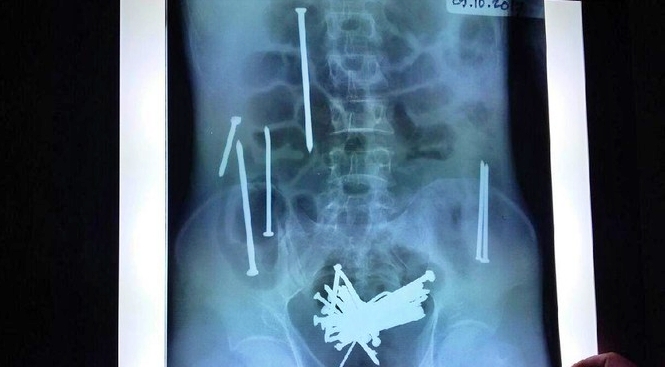

Hasil rotsen Penampakan paku dalam perut Wawan

Wawan diboyong keluarganya ke RS dr Soekardjo Tasikmalaya sebelas hari lalu setelah merasakan sakit di perutnya. Hasil rontgen memperlihatkan terdapat puluhan paku dalam perut Wawan. Sebanyak 48 paku berkarat di usus besar dan kecil Wawan berhasil dikeluarkan tim dokter. Nyawa Wawan tidak tertolong meski petugas medis berusaha maksimal memulihkannya. (*/detik)